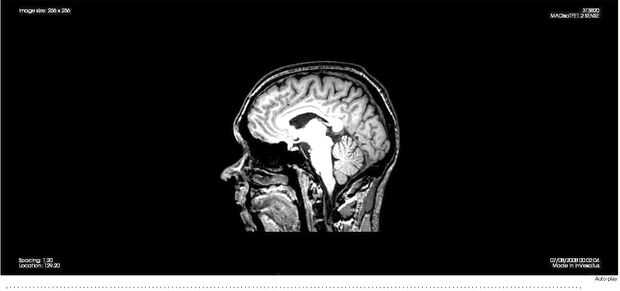

Lo hicimos con 3 InVesalius, una aplicación de código abierto médico (disponible para Windows y GNU Linux).

En primer lugar, importar sus archivos de imagen DICOM en rodajas a InVesalius. De datos altamente detallados deberá limitar el número de imágenes que se utilizan para generar el modelo 3D.

Invesalius enlace de descarga; http://svn.softwarepublico.gov.br/Trac/invesalius